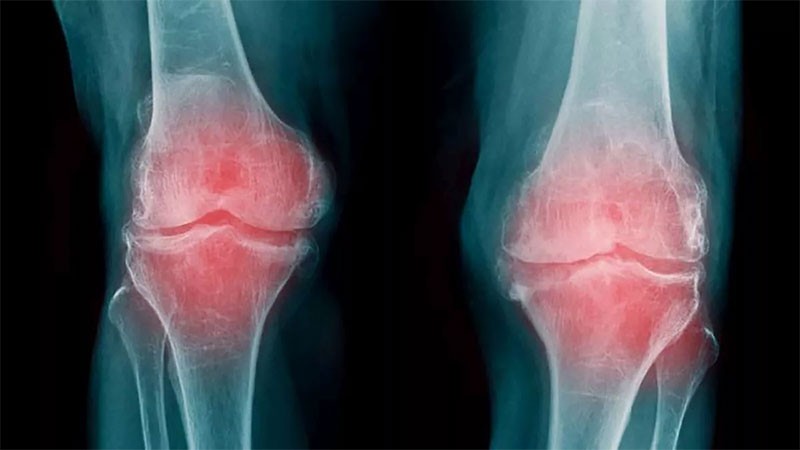

Consiguen identificar la progresión de la artrosis con un análisis de sangre

Un nuevo análisis de sangre que puede identificar la progresión de la artrosis de rodilla, y que es más preciso que los métodos actuales, fue anunciado por investigadores en la revista Science Advances, quienes además aseguraron que este método es una herramienta importante para avanzar en la investigación y acelerar el descubrimiento de nuevas terapias.

La prueba se basa en un biomarcador que llena un vacío importante en la investigación médica de una enfermedad común que actualmente carece de tratamientos eficaces.